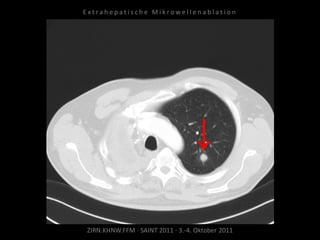

Patient: Männlich, 64 Jahre

Diagnose: Bronchial-Ca rechts, Z.n.

Pneumonektomie,

neu aufgetretene, solitäre, im Verlauf

progrediente Metastase im Oberlappen

links.

Ausgangsbildgebung:

CT vom 27.10.2010

Situation:

Nur eine Lunge und in dieser eine

(kleine) Metastase.

Ziel:

Destruktion der Metastase unter

Schonung eines möglichst großen

Lungenvolumens.

Indikation zur MWA:

Gezielte Positionierung unter CT-

Kontrolle, definiertes Wirkvolumen.

Ablation am 27.11.2010

1 Nadelposition.

Kontrolle nach MWA:

Parenchymeinblutung, Pneumothorax.

Noch im CT Anlage einer Pleuradrainage.

Patient am Abend beschwerdefrei.

Verlaufskontrolle:

CT 07.01.2011

Lungenmetastase gering

progredient.

CT 04.08.2011

Lungenmetastase deutlich progredient.

Neu diagnostizierte Hirnmetastase.

Resultat:

Metastase trotz Ablation

Fazit:

Beschränkung auf nur eine

Nadelposition kann – insbesondere in

der Lunge – nicht den nötigen

Sicherheitssaum gewährleisten, daher

auch bei kleiner Lungenmetastase

mehrere Nadelpositionen notwendig.